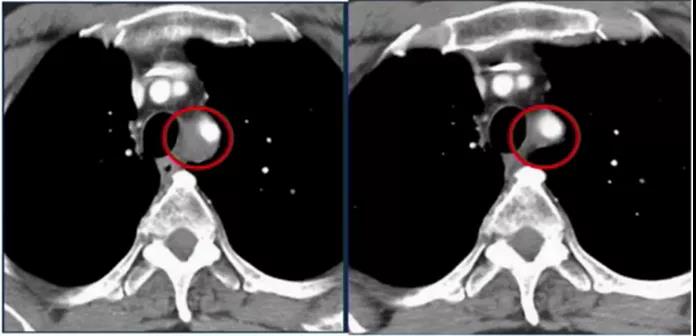

2020 年 AACR 大会上公布的一项研究表明,回输 TIL 之前,接受纳武利尤单抗治疗的 20 例患者仅 3 例患者肿瘤明显缩小;回输 TIL 后,大部分患者肿瘤明显缩小,其中 4 名患者持续 12 个月以上,1 例患者持续 24 个月以上。